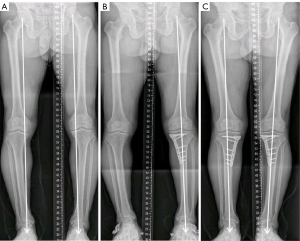

Bilateral standing anteroposterior whole-leg radiographs and anteroposterior, lateral, and axial radiographs were obtained from all patients before surgery and at the final follow-up. The whole-leg radiographs were acquired with a 14,351-inch cassette. The axial radiographs were obtained with knee flexion of 30° from the horizontal direction. As previously reported (3-5,12), measurements of the femoral tibial angle (FTA), medial proximal tibial angle (MPTA), and weight-bearing line percentage (WBLP) were obtained from whole-leg radiographs for the assessment of lower extremity alignment. FTA was measured as the angle formed by the intersection of the femoral and tibial mechanical axes. The femoral mechanical axis is the line from the center of the femoral head through the center of the knee, and the tibial mechanical axis is drawn as a line from the center of the ankle to the center of the knee (Figure 3). MPTA was the medial angle between two lines: one line of the tibial anatomical axis and a second line extending from the medial to the lateral most area of the tibial plateau, while excluding the osteophyte at the tibial plateau surface. Using a whole leg radiograph, the WBLP was calculated. The denominator was the width of the tibia as measured using a ruler, and the numerator was the tibial intersection of the weight-bearing line (with medial tibial edge at 0% and the lateral tibial edge at 100 %). Measurements of the Caton-Deschamps index (CDI) and Insall-Salvati index (ISI) were performed on a lateral view of the knee at a 30° flexion angle to assess the patellar height. Measurement of CDI and ISI were illustrated in Figure 4. Measurements of the lateral patellar tilt angle (LPTA) and lateral patellar shift (LPS) were illustrated in Figure 5. All images were imported into the same picture archiving and communications system. Measurements were made on radiographic images using standard digital tools, measuring to 0.1 accuracy (°). The image interpretation and measurements were performed by two senior readers (ML and ZL), who both had more than 10 years of experience in reading study radiographs. If readers disagreed on the measurements, readings were adjudicated by a panel of four readers (two non-author radiologists, ML and ZL).